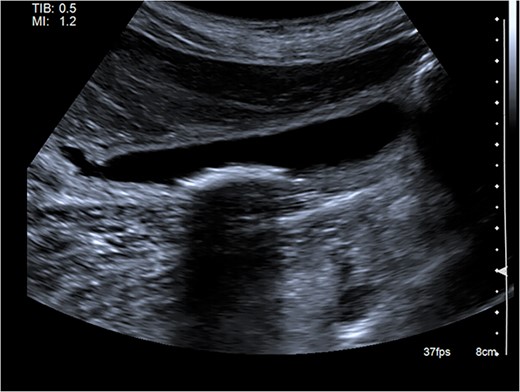

Right upper quadrant ultrasound revealed a distended gallbladder with multiple small calculi but no wall thickening nor pericholecystic fluid (Fig. 1). Intra- and extra-hepatic biliary ducts and the common bile duct were not dilated. A sonographic Murphy sign was not elicited. Computed tomography of her abdomen and pelvis revealed moderate hepatomegaly with heterogeneous enhancement, prominent hepatic veins, periportal edema and pericholecystic fluid (Fig. 2).

Abdominal ultrasound showing a distended gallbladder with multiple small calculi. There is no gallbladder wall thickening nor pericholecystic fluid.